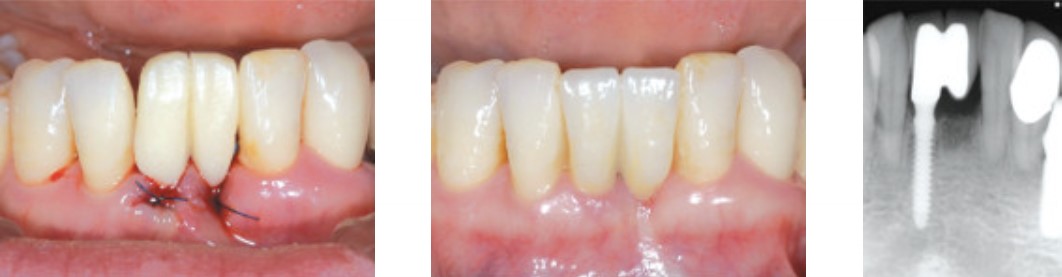

Временный протез, финальное протезирование через 4 мес.